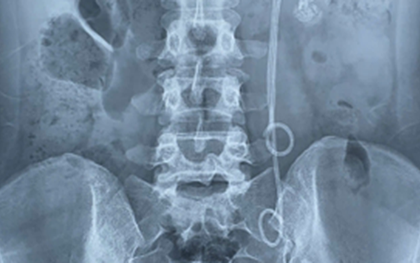

Bệnh viện Việt Nam - Thụy Điển Uông Bí (Quảng Ninh) vừa tiến hành phẫu thuật cắt bỏ thận trái bị mất chức năng do sỏi cho cụ bà 81 tuổi, trú tại Hải Dương.